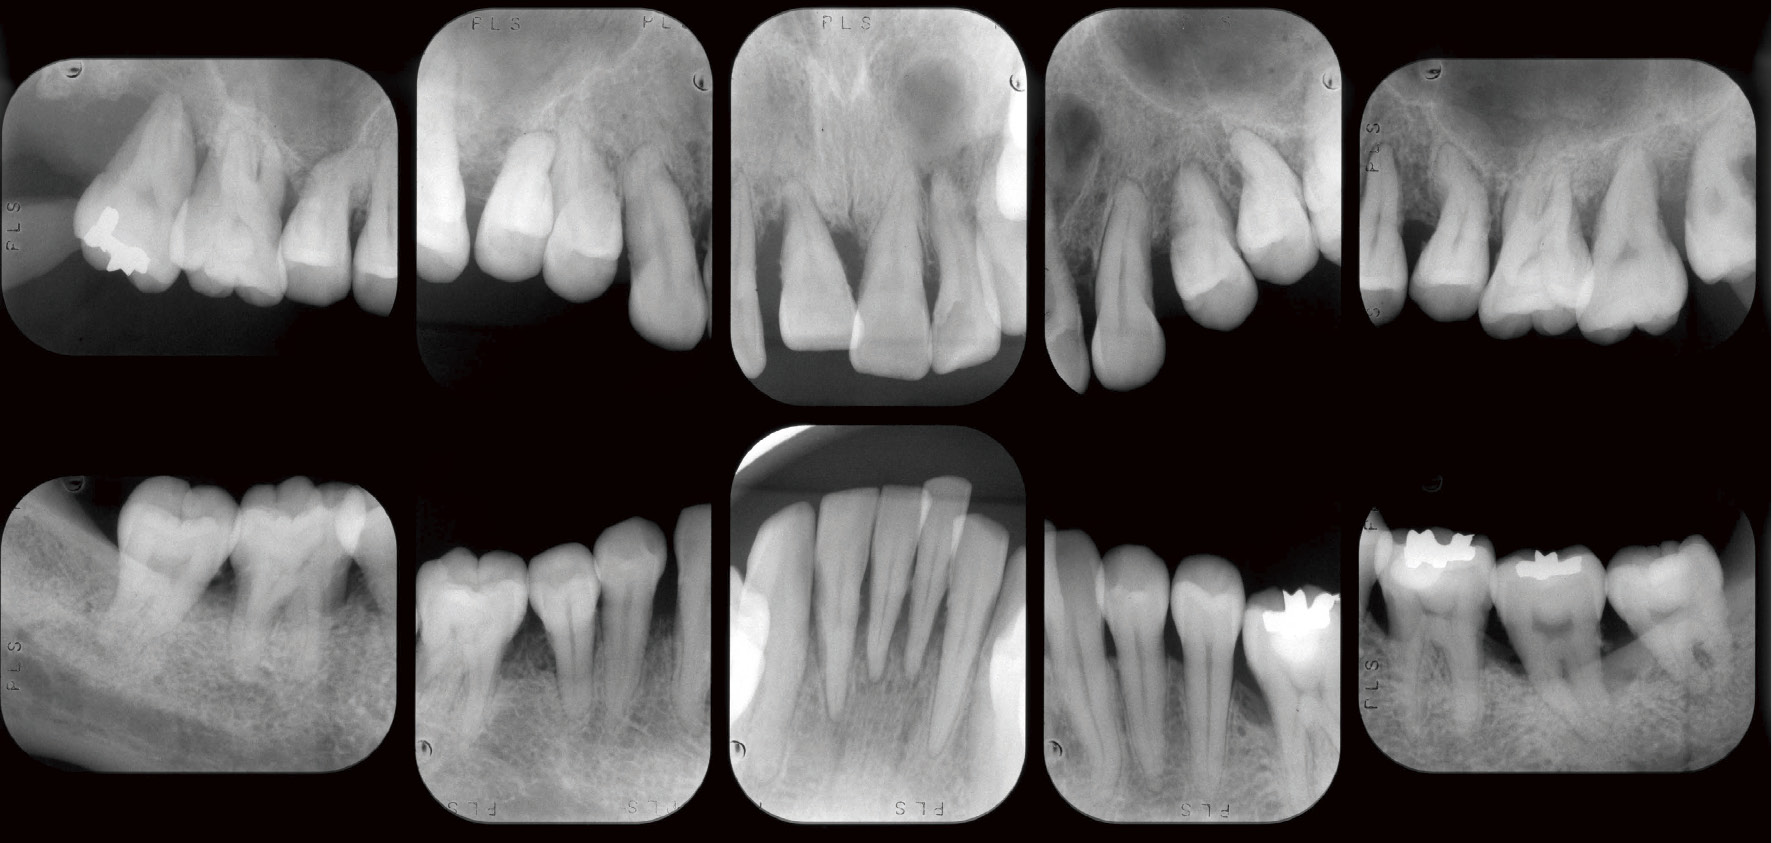

初診時デンタルエックス線写真

全顎にわたり歯根長の約1/2~2/3程度の水平性骨吸収像が認められ,17では根尖付近に至る骨吸収像が認められた。22には根尖部に透過像が認められた。